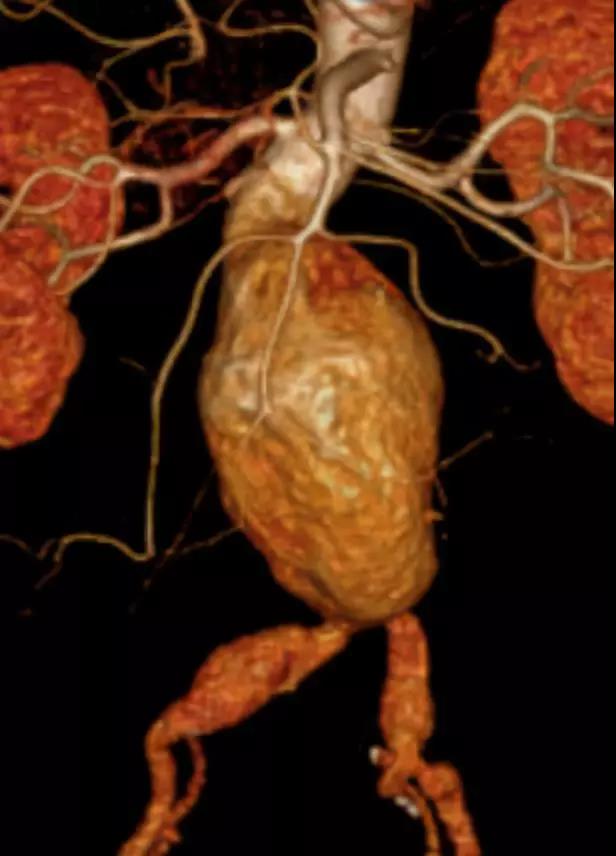

此次研究,纳入腹主动脉瘤的最大直径为85mm,平均直径为50.78mm;最短瘤颈长度为11mm,平均长度为31.34mm;最大肾下成角为74.6度,平均角度为32.48度。从动脉瘤最大直径变化来看,经过腹主动脉腔内治疗后,在出院前和术后6个月都有所减小。 在此次研究中,彩神在线网信彩票-彩神通免费版下载-彩神8争霸vlll-彩神购彩购彩大厅-彩神软件陆立根免费版-彩神ll争霸3-彩神ll彩神8-彩神ll争霸彩票-拼搏在线彩神网网页版Yuranos™新一代腹主动脉覆膜支架系统临床试验初步展现了优秀的临床试验结果,其30天内MAE发生率低,安全性得以验证;而且由于该产品的柔顺性有较大提升,输送器直径减小,对于短瘤颈和角度大的病例是更好的选择。 入组病例展示: 病例一:男性,年龄69岁,既往高血压,糖尿病病史。术前腹主动脉瘤直径67.3mm,近端瘤颈长度23.2mm,近端锚定区直径21.2mm,肾下成角60.5度。 术中从右侧股动脉穿刺,选用彩神在线网信彩票-彩神通免费版下载-彩神8争霸vlll-彩神购彩购彩大厅-彩神软件陆立根免费版-彩神ll争霸3-彩神ll彩神8-彩神ll争霸彩票-拼搏在线彩神网网页版型号为AB-2412-50-120的主体支架,支架近端定位于右肾动脉开口处,后释放打开裸支架,并向下释放主体短分支,左侧输送进入彩神在线网信彩票-彩神通免费版下载-彩神8争霸vlll-彩神购彩购彩大厅-彩神软件陆立根免费版-彩神ll争霸3-彩神ll彩神8-彩神ll争霸彩票-拼搏在线彩神网网页版髂动脉延长支架IE-1416-100,并释放,保留左侧髂内动脉。接着释放主体长分支,右侧输送进入彩神在线网信彩票-彩神通免费版下载-彩神8争霸vlll-彩神购彩购彩大厅-彩神软件陆立根免费版-彩神ll争霸3-彩神ll彩神8-彩神ll争霸彩票-拼搏在线彩神网网页版髂动脉延长支架IE-1424-80,并释放,保留右侧髂内动脉。 手术顺利,无内漏,持续时间1小时10分钟。术后CTA检查,支架形态良好,无内漏。详见下图: 术前影像 术中影像 出院前影像 术后6个月影像 术后1年影像 病例二:女性,年龄72岁,既往高血压,静脉曲张病史。术前腹主动脉瘤直径48.81mm,近端瘤颈长度16.15mm,近端锚定区直径18.43mm,肾下成角66度。 术中从右侧股动脉穿刺,选用彩神在线网信彩票-彩神通免费版下载-彩神8争霸vlll-彩神购彩购彩大厅-彩神软件陆立根免费版-彩神ll争霸3-彩神ll彩神8-彩神ll争霸彩票-拼搏在线彩神网网页版型号为AB-2412-50-140的主体支架,支架近端定位于右肾动脉开口处,后释放打开裸支架,并向下释放主体短分支,左侧输送进入彩神在线网信彩票-彩神通免费版下载-彩神8争霸vlll-彩神购彩购彩大厅-彩神软件陆立根免费版-彩神ll争霸3-彩神ll彩神8-彩神ll争霸彩票-拼搏在线彩神网网页版髂动脉延长支架IE-1414-120,并释放,保留左侧髂内动脉。接着释放主体长分支,右侧输送进入彩神在线网信彩票-彩神通免费版下载-彩神8争霸vlll-彩神购彩购彩大厅-彩神软件陆立根免费版-彩神ll争霸3-彩神ll彩神8-彩神ll争霸彩票-拼搏在线彩神网网页版髂动脉延长支架IE-1414-80,并释放,保留右侧髂内动脉。